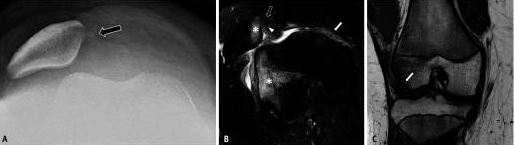

La luxation aiguë de la rotule (APLD) est la forme la plus grave de PFI.Le film simple radiographique montre la découverte de lésions aiguës, qui peuvent inclure un épanchement articulaire, un niveau lipidique occasionnel d'arthropathie graisseuse, une fracture de la rotule médiale ostéochondrale, une inclinaison latérale/subluxation de la rotule (Figure 8A) et un signe de sillon latéral profond causé par lésion par impaction du cartilage condylien fémoral latéral.Les manifestations IRM spécifiques de la LPD aiguë comprennent une lésion du stabilisateur médial (observée dans 96 %), une inclinaison rotulienne latérale ou une subluxation, une lésion ostéochondrale et un épanchement articulaire (Figure 2B, C).Dans la plupart des cas, la rotule est réinitialisée spontanément après la première luxation.

Jusqu'à 70 % des patients subiront une luxation récurrente, et une luxation récurrente chronique peut survenir.Dans ce cas, l'IRM peut montrer une déchirure chronique du stabilisateur médial, une déformation rotulienne médiale, une ossification de la rotule médiale, un impact de graisse rotulienne-fémorale, une lésion du cartilage et une dégénérescence de l'articulation fémoro-patellaire latérale (Figure 3).